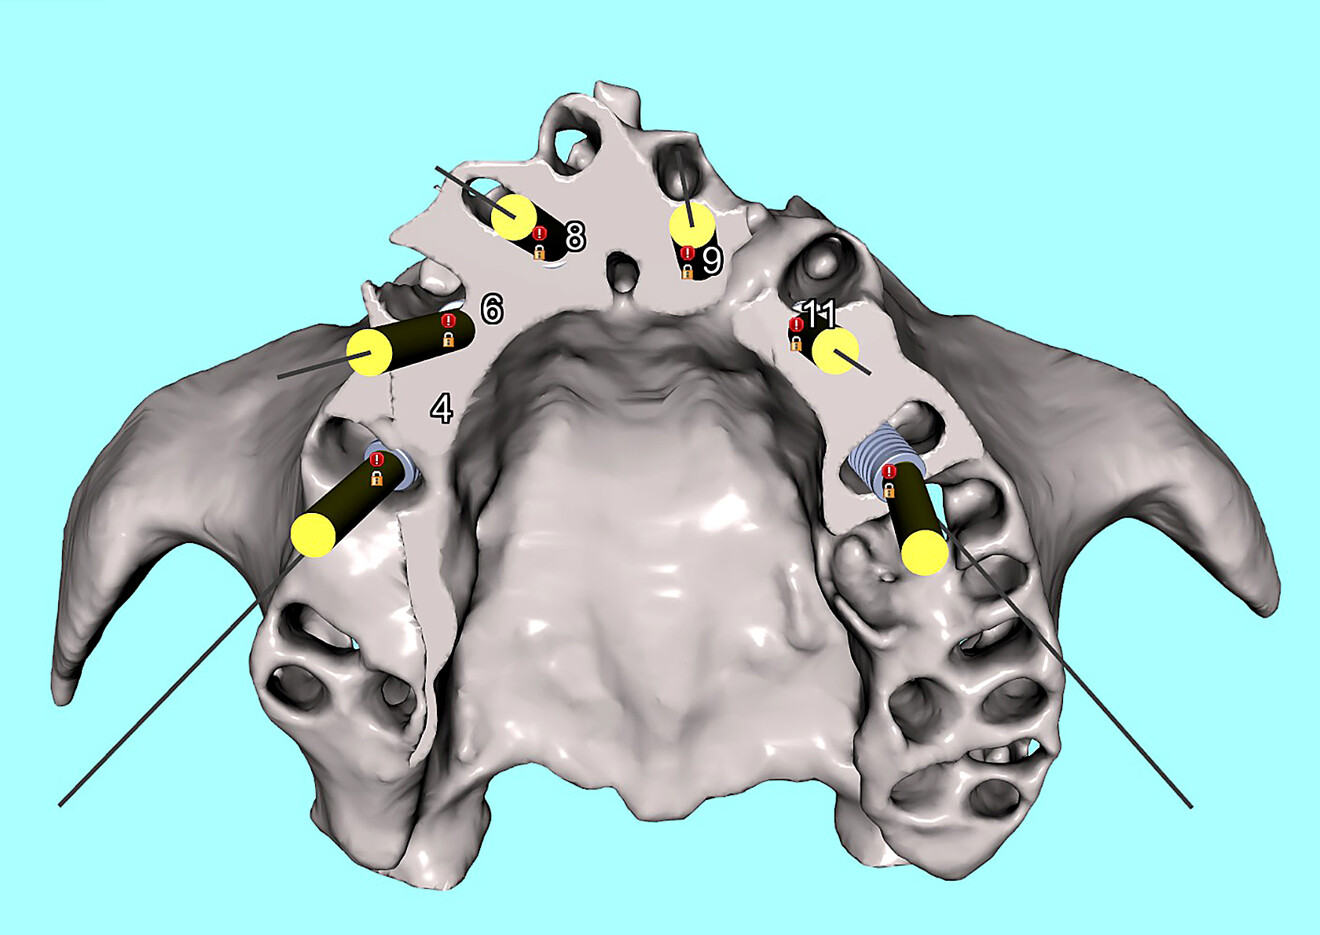

An innovative and novel surgical guide was designed for the maxillary arch using Blue Sky Plan and a free STL editor, MeshMixer (Autodesk). The guide was designed on the 3D reconstructed model from segmented data in Blue Sky Plan (Fig. 7a). The unique aspect of the guide comes from the anterior rest seats that rotate into place from the buccal aspect of the maxillary bone (Fig. 7b). The rotational path design allows for the guide to intimately contact the buccal bone and then rotate until seated posteriorly and positively on two rest stops (Figs. 8a & b). The guide would be fairly stable once seated on the alveolar ridge, but would require the additional stability gained from a single anchor pin placed directly into the nasopalatine canal (Fig. 9).

Fig. 7a: Simulation of the novel rotational path nasopalatine canal pin guide (blue) seated on the maxillary bone. Frontal view with selective transparency to visualise implant locations.

Fig. 7b: Simulation of the novel rotational path nasopalatine canal pin guide (blue) seated on the maxillary bone. Occlusal view illustrating the three buccal supports with rest seats (yellow arrows).

Fig. 9: Exploded view of the nasopalatine canal pin, the nasopalatine canal pin guide (blue) and the maxillary bone showing anterior bony concavities.